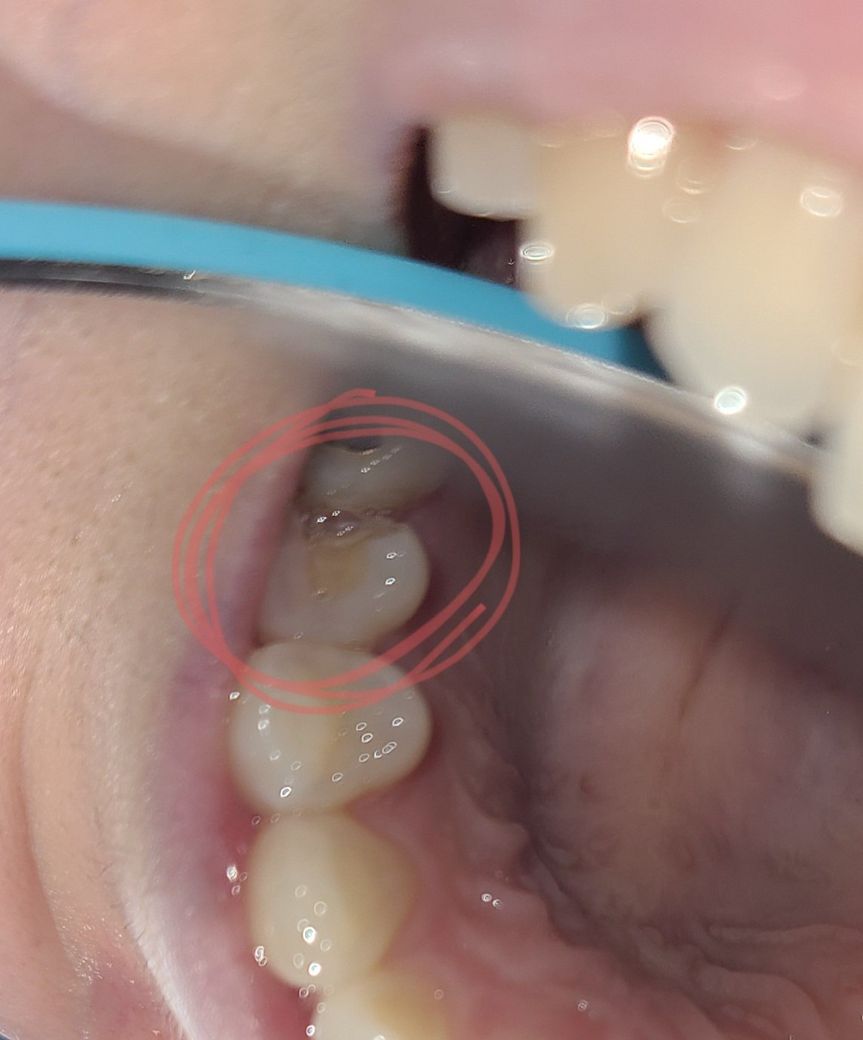

임시재료로 메꿔 둔 것이 떨어진 상황으로 보입니다.

인레이 한곳이 임시재료가 탈락된것으로 보입니다.

해당 부위는 음식물이 끼기 쉽고 충치가 쉽게 발생할 수 있기 때문에 당연히 칫솔질을 잘 해줘야 합니다.

다만 치아가 시릴 수 있고 깨질 수 있으므로 부드럽게 칫솔질을 해 주시는 것이 좋으며, 다시 내원하는 기간이 길지 않으므로 해당 기간 사이에 큰 문제가 발생할 것으로 보이지는 않습니다.

해당부위를 양치하는것이 좋지만, 시릴가능성이 높기때문에 우선 가글만이라도 잘 해주시는게 좋습니다.